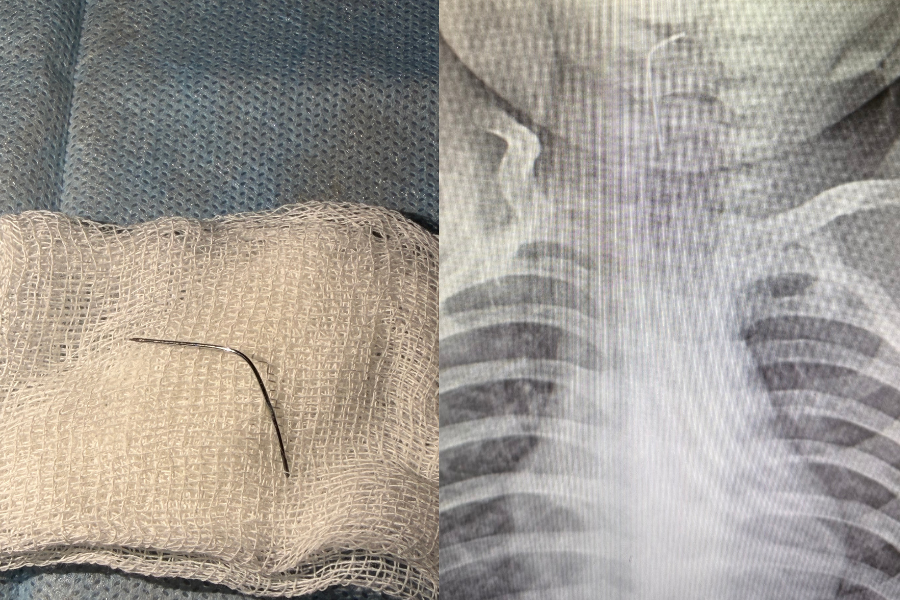

Фото: Түркістан облысы Денсаулық сақтау басқармасы

"Сәби абайсызда ине жұтып қойған. Дәрігерлер дереу рентгенологиялық тексеріс жүргізіп, бөгде заттың нақты орналасқан орнын анықтады. Түркістан облыстық балалар ауруханасының мамандары - хирург Мұхағали Темірбеков пен эндоскопист Бабыр Ырысқұлов өңеште тұрып қалған инені алды", - деп жазылған хабарламада.

Қазір баланың жағдайы жақсы. Сәби дәрігерлердің бақылауында болып, кейін үйіне шығарылған.